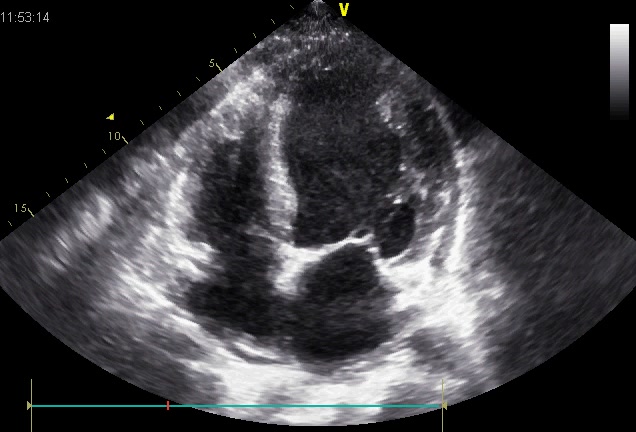

右冠状动脉